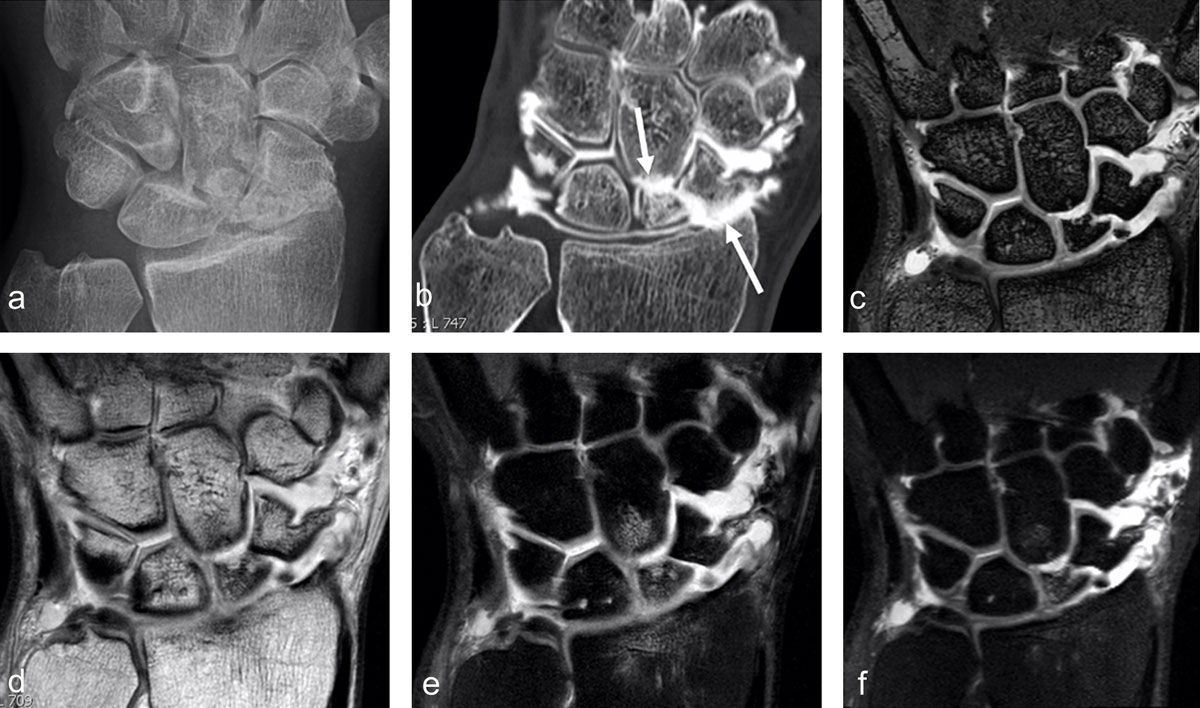

Figure 4

SNAC 2 wrist after scaphoid fracture with nonunion in a 41-year-old man. Secondary cartilage degeneration is first seen in the radioscaphoid compartment (b, arrow pointing up) and later in the scaphocapitate midcarpal joint space (b, arrow pointing down) on conventional radiograph and much better on CT-arthrography (b). MRI well demonstrates the nonunion (on 3D DESS with 0.4mm sections) and increased signal in the proximal scaphoid pole on 2D (e) and 3D (f) proton-density fat-saturated images, corresponding to edema and indicating that the separated fragment might be unstable (and painful). Subchondral bone marrow edema is also detected in the proximal pole of the capitate under the cartilage loss and in the distal radius (e).